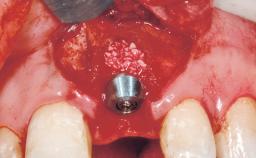

Immediate Flapless Placement of an Implant in a Maxillary Right Lateral Incisor Site

This 43-year-old male patient, a non-smoker, came to our practice because of a fracture of tooth 12 caused by a bicycle accident. Due to the combined para- and infrabony crown and root fracture, tooth extraction, and subsequent implant placement were suggested to the patient as the therapy of choice. The patient had high esthetic expectations with regard to the treatment outcome and asked for an immediate fixed provisional restoration. His individual esthetic risk profile summed up to a medium esthetic risk.

Placement Protocol Immediate implant placement

Socket Integrity Sufficient, with intact bone walls

Bone Volume Sufficient, with intact walls